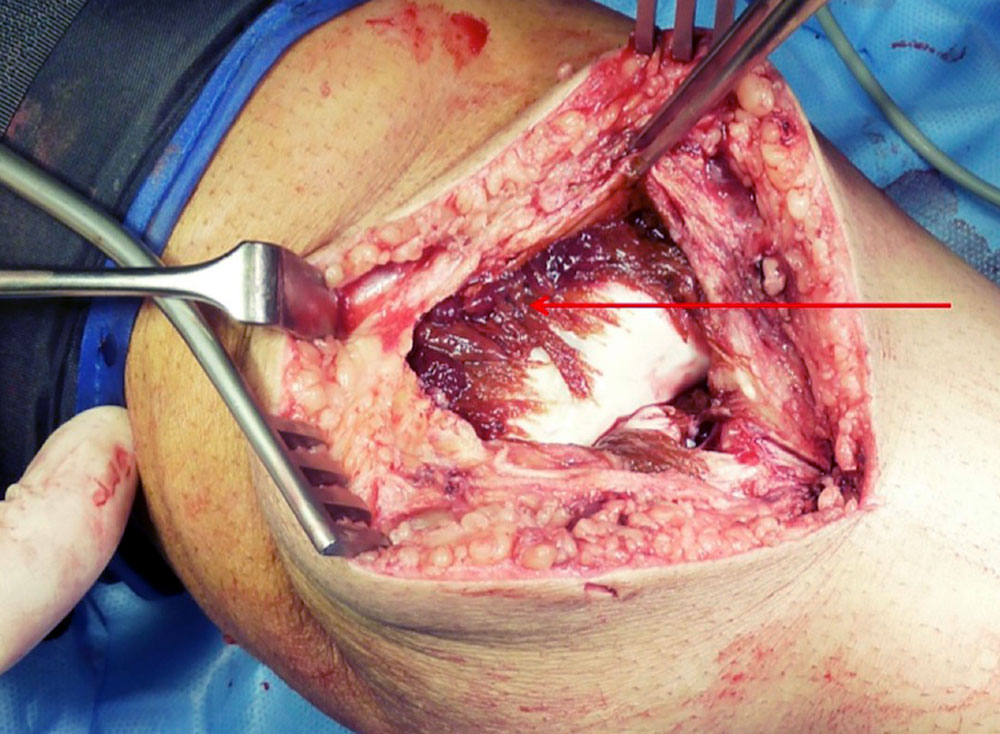

Treatment should always be interdisciplinary. On the one hand, it requires interventional therapy of the peri-articular, or if possible intra-articular, vascular malformation to close vascular connections into the affected joint and to facilitate surgical access. On the other hand, it requires surgical removal of the peri- and intra-articular malformation and the altered synovium (synovectomy), if possible.

Surgical therapy can be either arthroscopic or open. Although the arthroscopic approach has clear advantages in terms of postoperative rehabilitation, it often cannot be used because of the extensive findings and more difficult bleeding control. Essentially, two factors play a role in why an open procedure must often be chosen:

• Large intra-articular vascular malformations with bleeding (even with a tourniquet in place) additionally worsen the arthroscopic overview.

If destruction of the cartilage has already occurred, cartilage replacement therapy must be performed in addition to resection of the malformation and synovectomy. However, in most cases this no longer represents a curative approach, but can often only delay the development of osteoarthritis.